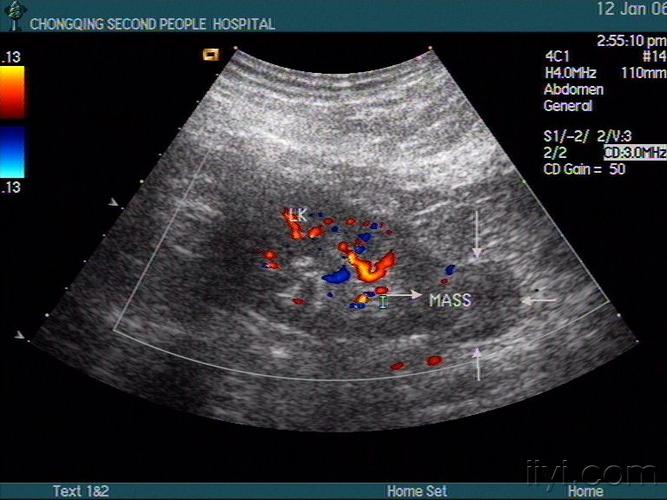

长不大的肾肿瘤 - 超声医学讨论版 - 爱爱医医学论坛

一例后肾腺瘤超声表现病例分析

各类肾脏病超声图像表现